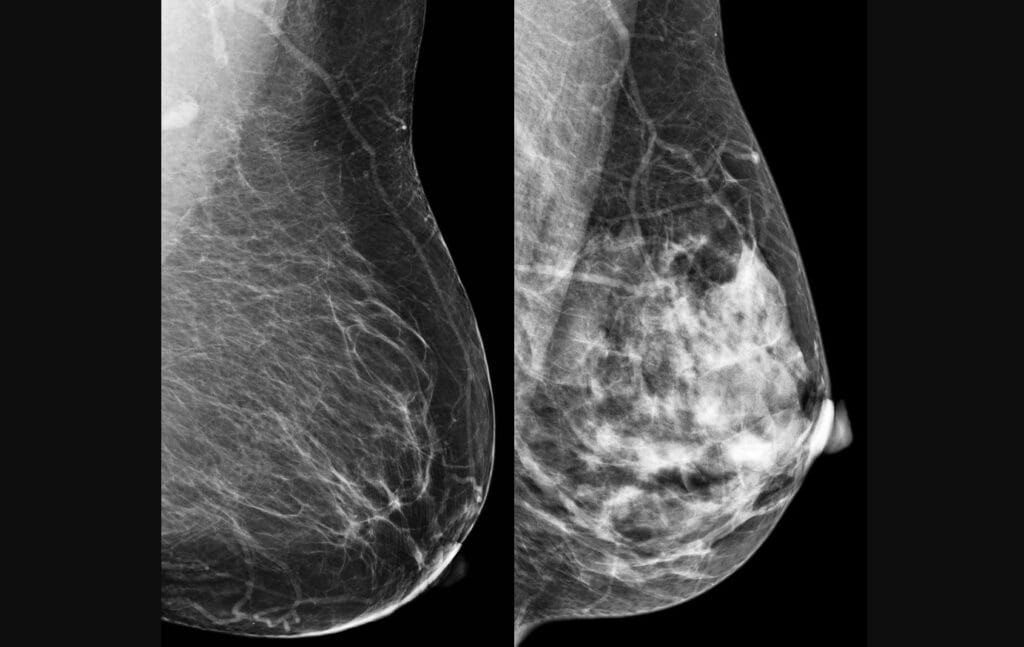

Com os resultados, é possível indicar uma maior regularidade de exames de rotina, como mamografia, no Norte e Nordeste do Brasil. “Os dois anos indicados atualmente no Sistema Único de Saúde (SUS) podem ser muito tempo para quem estiver com um tumor triplo-negativo, que duplica de tamanho com muita rapidez. O ideal seriam exames anuais”, encerra Vieira.